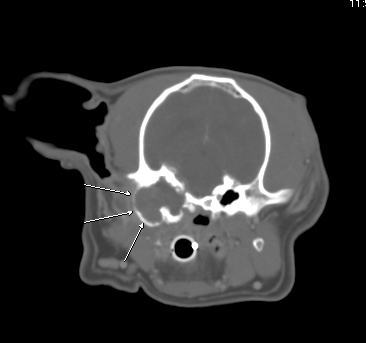

Fig 1:

Transverse CT showing expanded and irregular, tissue filled left tympanic bulla